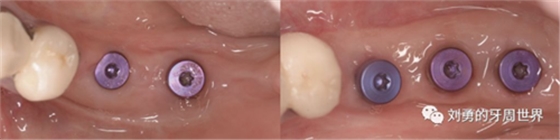

但是該方法對于縫合技術要求較高,因此本人嘗試了新的方法,膜釘固定:

該方法操作簡單,但是需要擇期局麻下拆除膜釘。